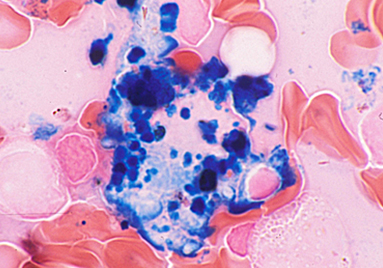

診断材料 骨髄

光顕的所見 マクロファージの旺盛な鉄の取り込みは鉄利用能の悪さがうかがえる。

【Fe.×1000】